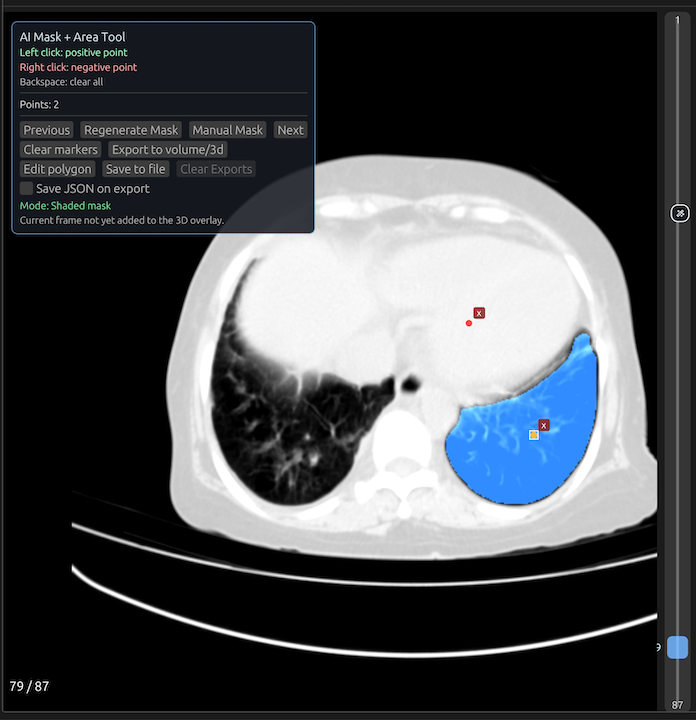

3. Start with AI-powered segmentation when the borders are reasonably distinct from surrounding structures.

AI assistance is most useful when the structure has recognizable contrast from surrounding tissue and you want to reduce time spent tracing. A good AI-first workflow gives you an initial region quickly, then lets you correct only what matters.

Place positive points with left click inside the ROI so the model understands what should be included in the mask. And use right click to place negative points outside ROI that needs to be excluded.

When surrounding tissue is being pulled into the mask, place negative points with right click on adjacent structures that should be excluded. This often improves separation without requiring a full redraw.